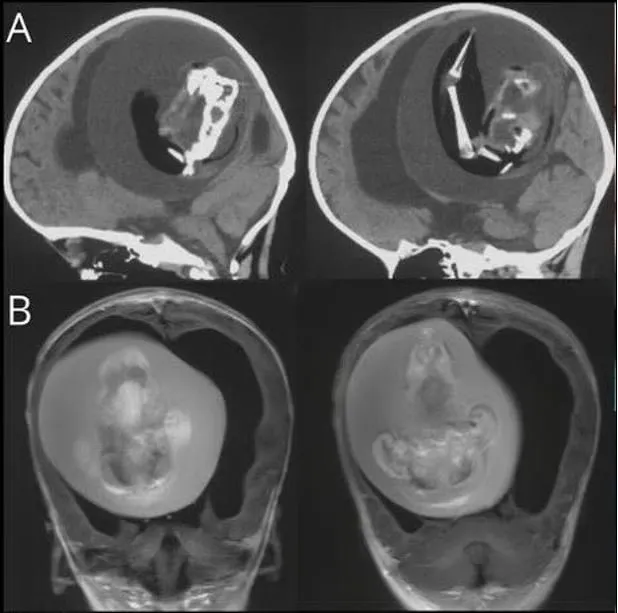

Çin'de bir yaşındaki bebeğin beyninden ikizinin fetüsü çıkarıldı. Bunun tarihte yalnızca birkaç kez yaşanan bir anomali olduğunu dile getiren uzmanlar, bebeğin kafatasının beklenenden daha geniş olması nedeniyle durumun fark edildiğini belirtti.

Tıp literatüründe yalnızca birkaç kez ortaya çıkan ilginç bir olay yaşandı. Çin'de bir yaşındadaki bir bebeğin kafatasının beklenenden geniş olduğu ve motor becerilerinde sorunlar görüldüğü gerekçesi ile hastaneye kaldırılmıştı. Bebeği hastalığı şaşkına çevirdi.

Emekleme, ayakta durma, yürüme, koşma, salınım, dönme, yuvarlanma, zıplama ve denge kurma gibi hareketlerin gerçekleştirilmesini sağlayan motor becerilerini gerçekleştiremeyen bebeğin kafatasında ikiz kardeşi olduğu tespit edildi.

Bebeğin beyninin sıkıştığı ve içinde sıvı birikimi olduğu tepsit edilinceileri incelemeler yapıldı.